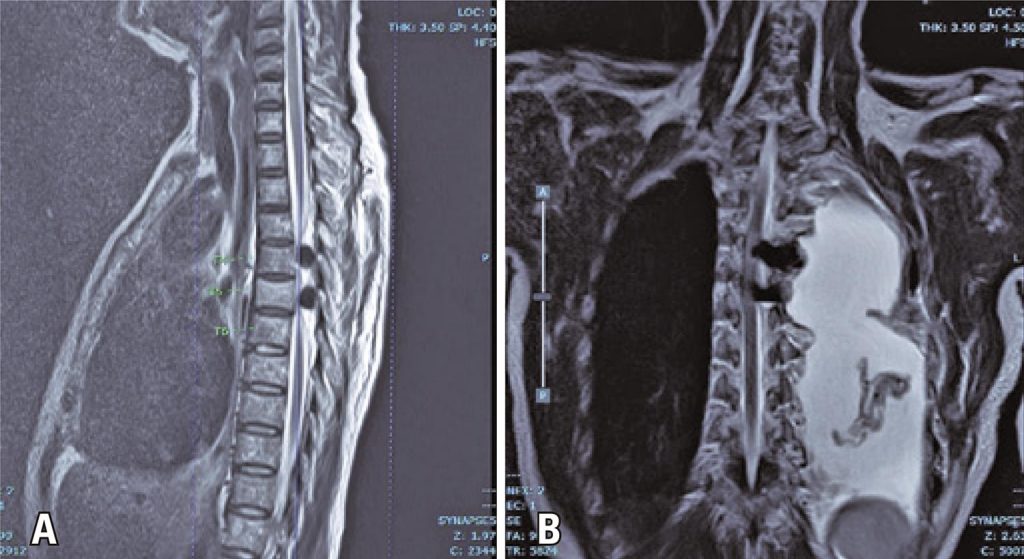

Post-thoracotomy paraplegia after non-aortic surgery is an extremely uncommon complication. A 56-year-old woman presented with a 1-year history of progressive shortness of breath. Computed tomography revealed a locally advanced posterior mediastinal mass involving the ribs and the left neural foramina. Tumor excision with a left pneumonectomy was performed. Post-resection, bleeding was noted in the vicinity of the T4-T5 vertebral body, and the bleeding point was packed with oxidized cellulose gauze (Surgicel®). Postoperatively, the patient complained of bilateral leg numbness extending up to the T5 level, with bilateral paraplegia. An urgent laminectomy was performed, and we noted that the spinal cord was compressed by two masses of Surgicel® with blood clots measuring 1.5 × 1.5cm at T4 and T5 levels. The paraplegia did not improve despite the removal of the mass, sufficient decompression, and aggressive postoperative physiotherapy. Surgeons operating in fields close to the intervertebral foramen should be aware of the possible threat to the adjacent spinal canal as helpful hemostatic agents can become a preventable threat.